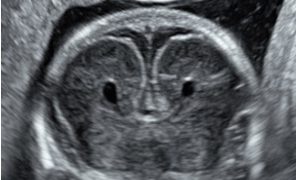

Guida al Counselling di Maggio 2025: patologie cistiche della fossa cranica posteriore

Cari colleghi, vi presentiamo la guida al counseling di Maggio 2025 sulla Patologia cistica della fossa cranica posteriore. Potrete scaricarla cliccando sul link. Grazie a Laura Sarno! ...